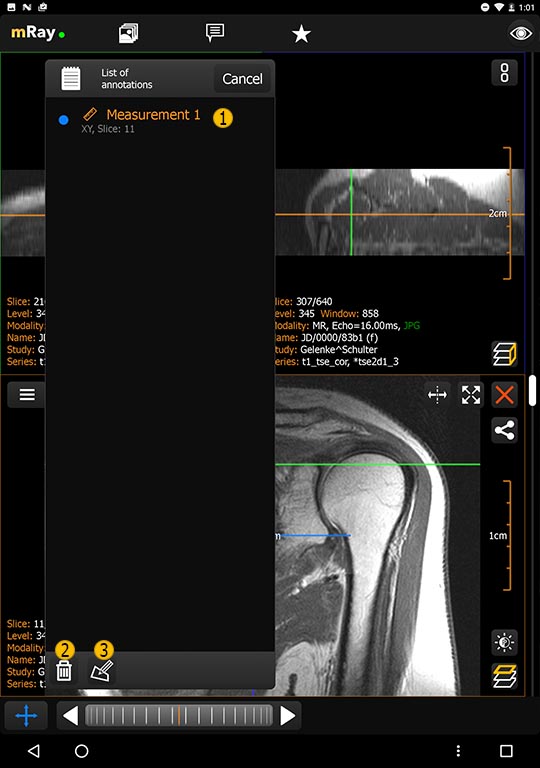

11.1.2. Annotation menu

The following button (see List of annotations) will appear in the Toolmenu if the user has created any annotations.

-

Opens the 'List of annotations' window

-

A single tap selects and jumps to the annotation. Tap and hold will open the annotation submenu (Item 2,3).

-

Deletes the selected annotation.

-

Edit the name of the currently selected annotation.